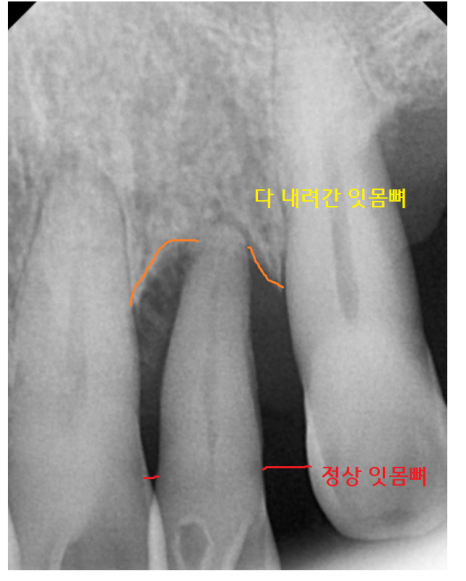

잇몸뼈가 녹아서

뽑아야 할 치아가 있었습니다.

전반적으로 남아있는 잇몸뼈가 없어서

철저한 디지털 분석이 필요했습니다.

특히나 상악 치아

윗니는 상악동 염증으로 인해

잇몸뼈가 많이 없었는데요.